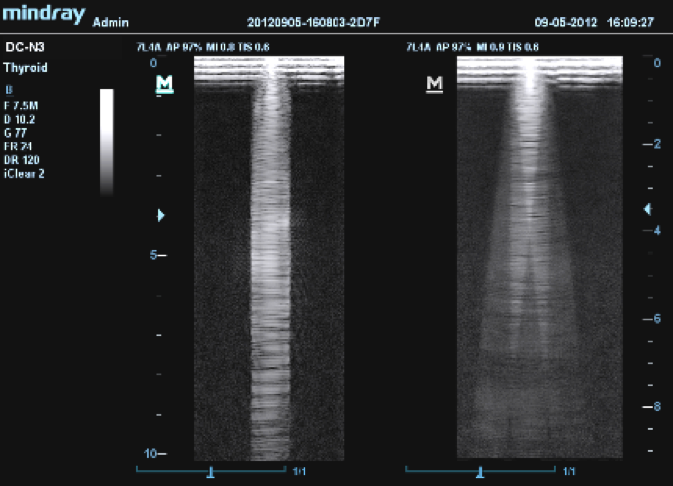

Принцип работы многолучевого составного сканирования (компаундинга) заключается в объединении кадров, полученных при генерации ультразвука под разными углами.

Предлагаем вам ознакомиться с примером применения данной технологии. Изображения выполнены на приборе Mindray DC-8, на верхнем изображении режим iBeam (компаундинг) отключен, а на нижнем включен на первую ступень регулировки (3 луча).